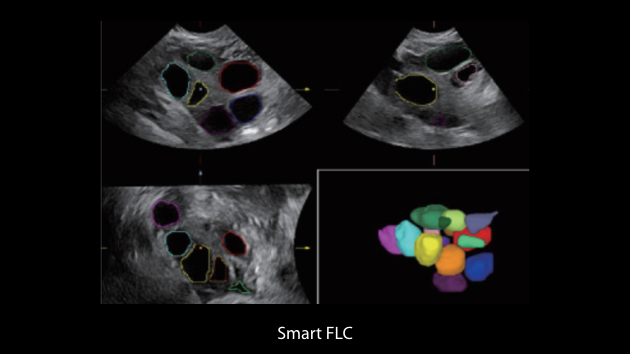

Gambar Klinis